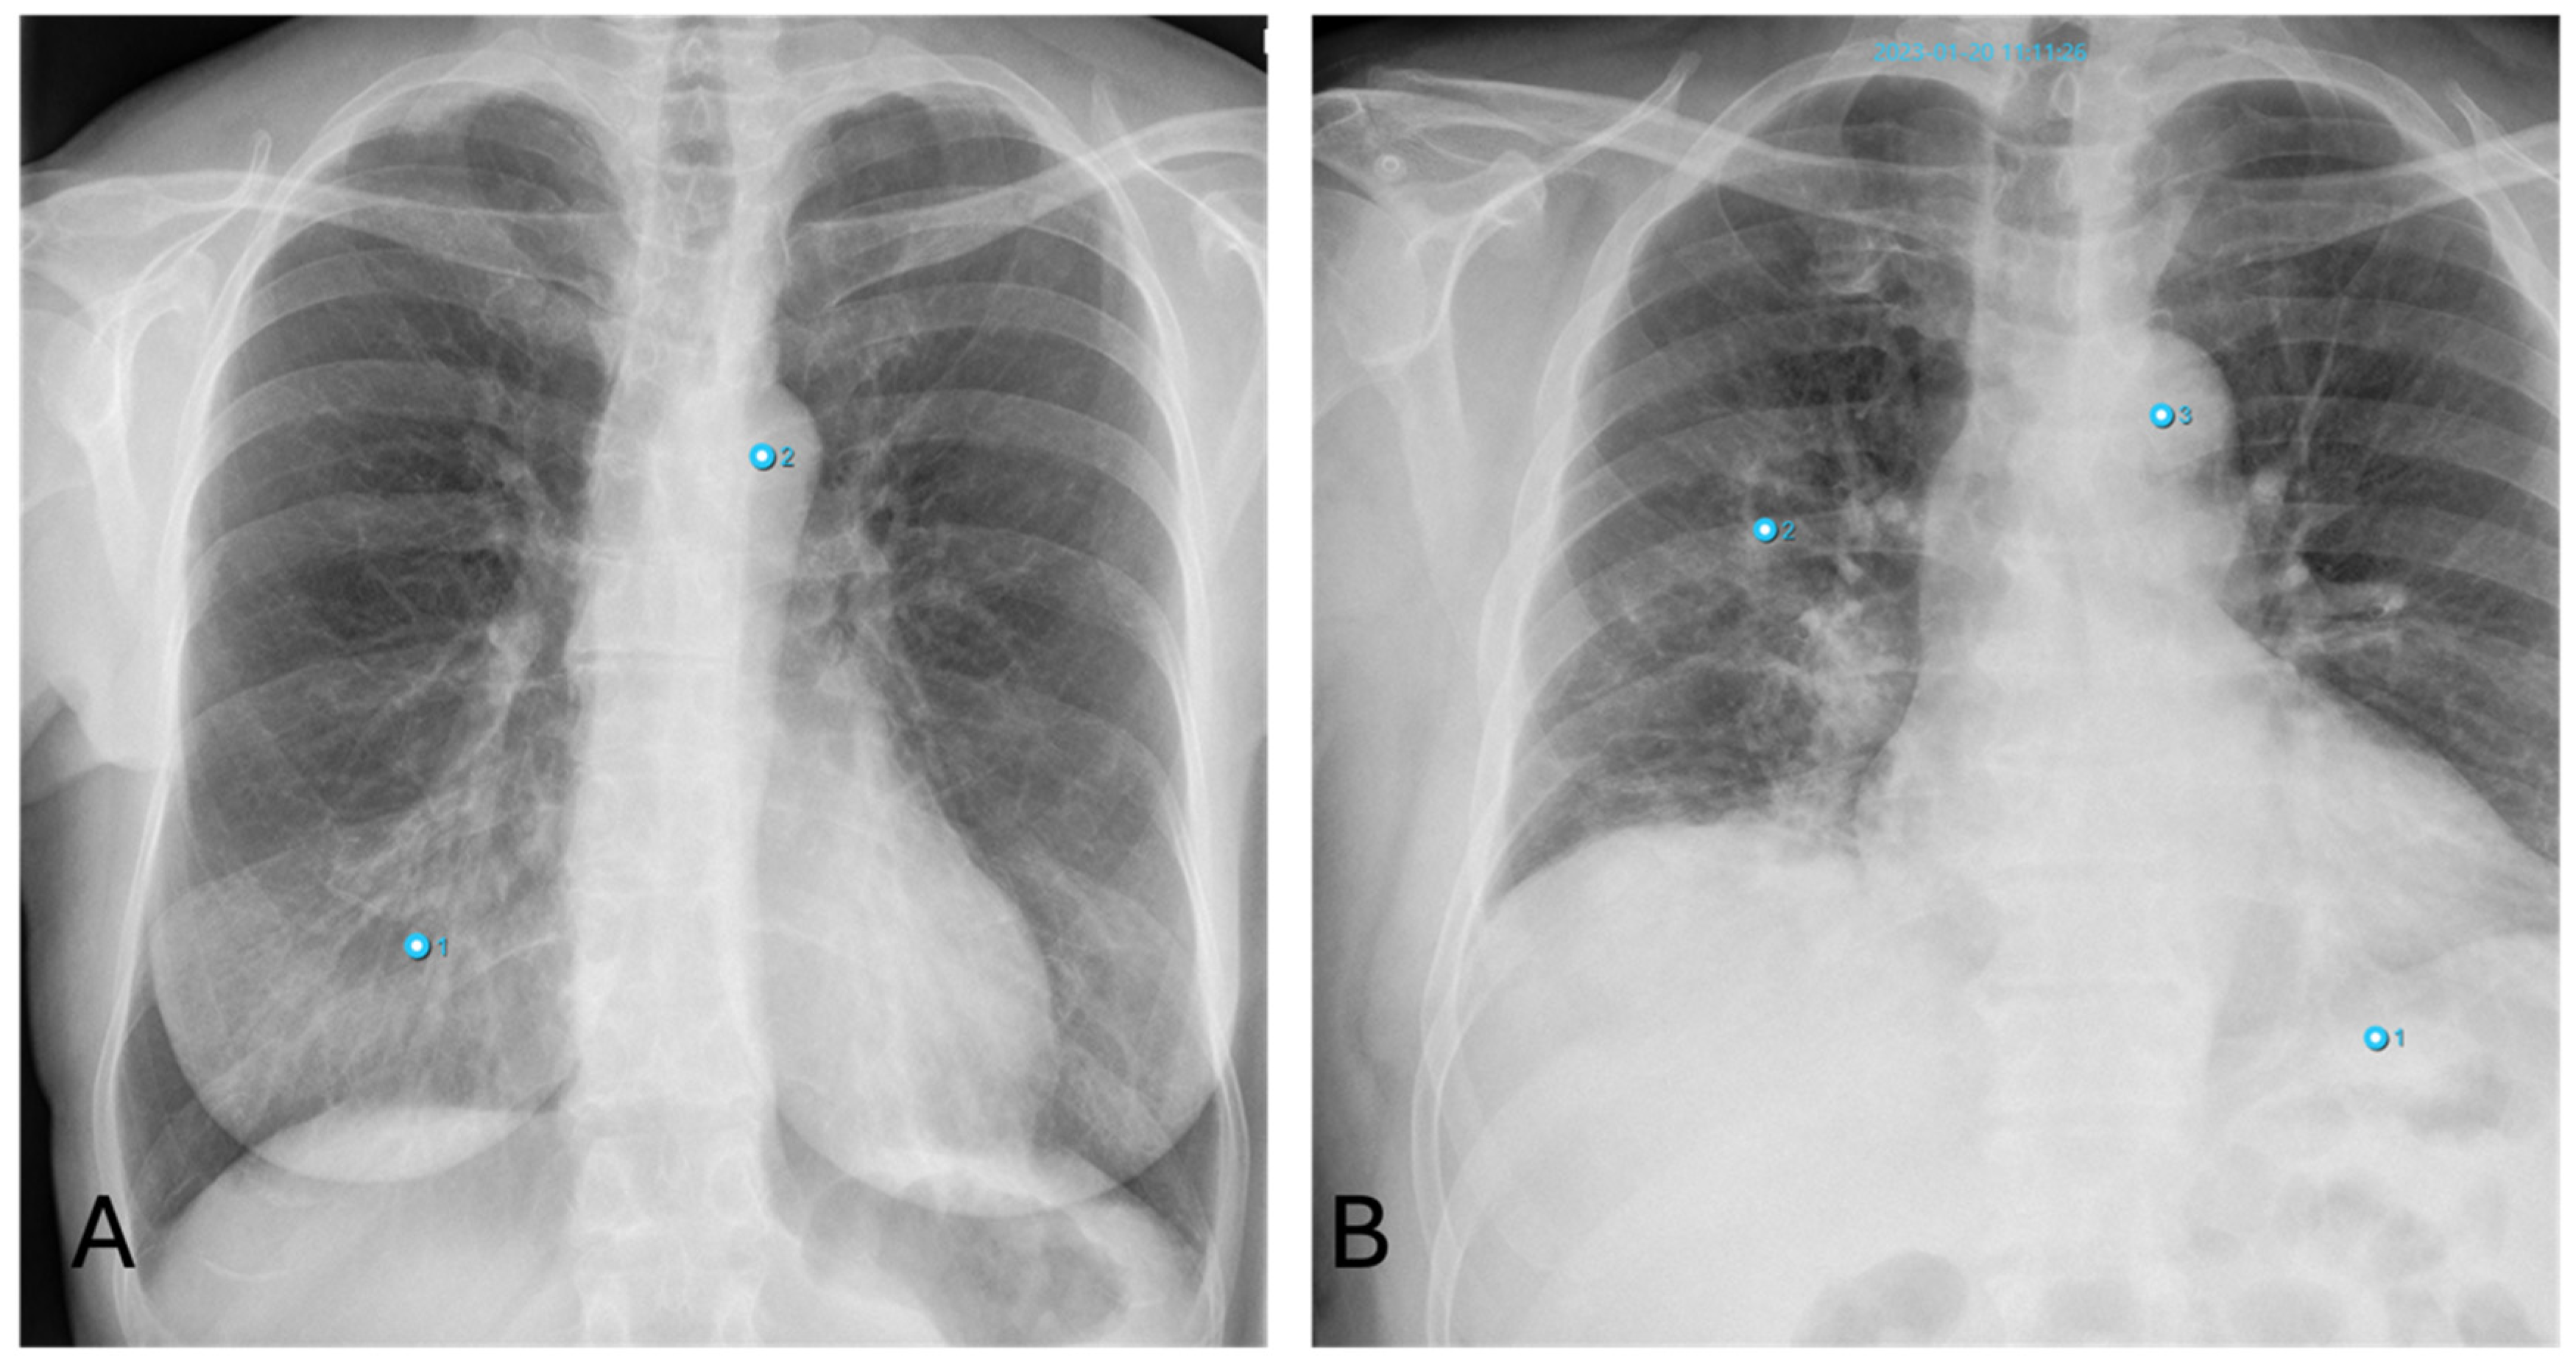

3.4.1. Fractures

A frequent mistake made by the AI is interpreting the joint surfaces of the shoulder depicted in different projections, as well as projections of the scapula onto the thorax, as fracture lines due to their alignment with the thorax. False positive findings can also occur because of the superimposition of bones with foreign material, such as catheters.

On the other hand, vertebral fractures are most often overlooked by the AI because these are best assessed in the lateral view, whereas the software only takes the PA view into account. Examples of false positive and negative osseous findings are shown in Figure 5.

All in all, thoracic fractures are a subset of pathologies which are often overlooked by radiologists (see Figure 5D), who rather turn their attention to lung pathologies—a fact which is substantiated by our results showing a high number of fractures detected by AI alongside a low agreement with the human rater (see Figure 3).

Figure 5. Inconsistencies of fracture diagnoses: (A)—false-positive fracture of the right clavicle described by AI at the overlay of the clavicle and 2nd rib (pneumonia in the left basal lung was correctly identified); (B)—false-positive fracture description of the 10th rib on the right by AI due to overlay of external oxygen hose; (C)—false-negative bone status; fracture of the left clavicle was not described by AI (Note: other finding incorrectly labelling “aortic abnormality”); (D)—rib fracture on the right found by AI but overlooked by radiologists.